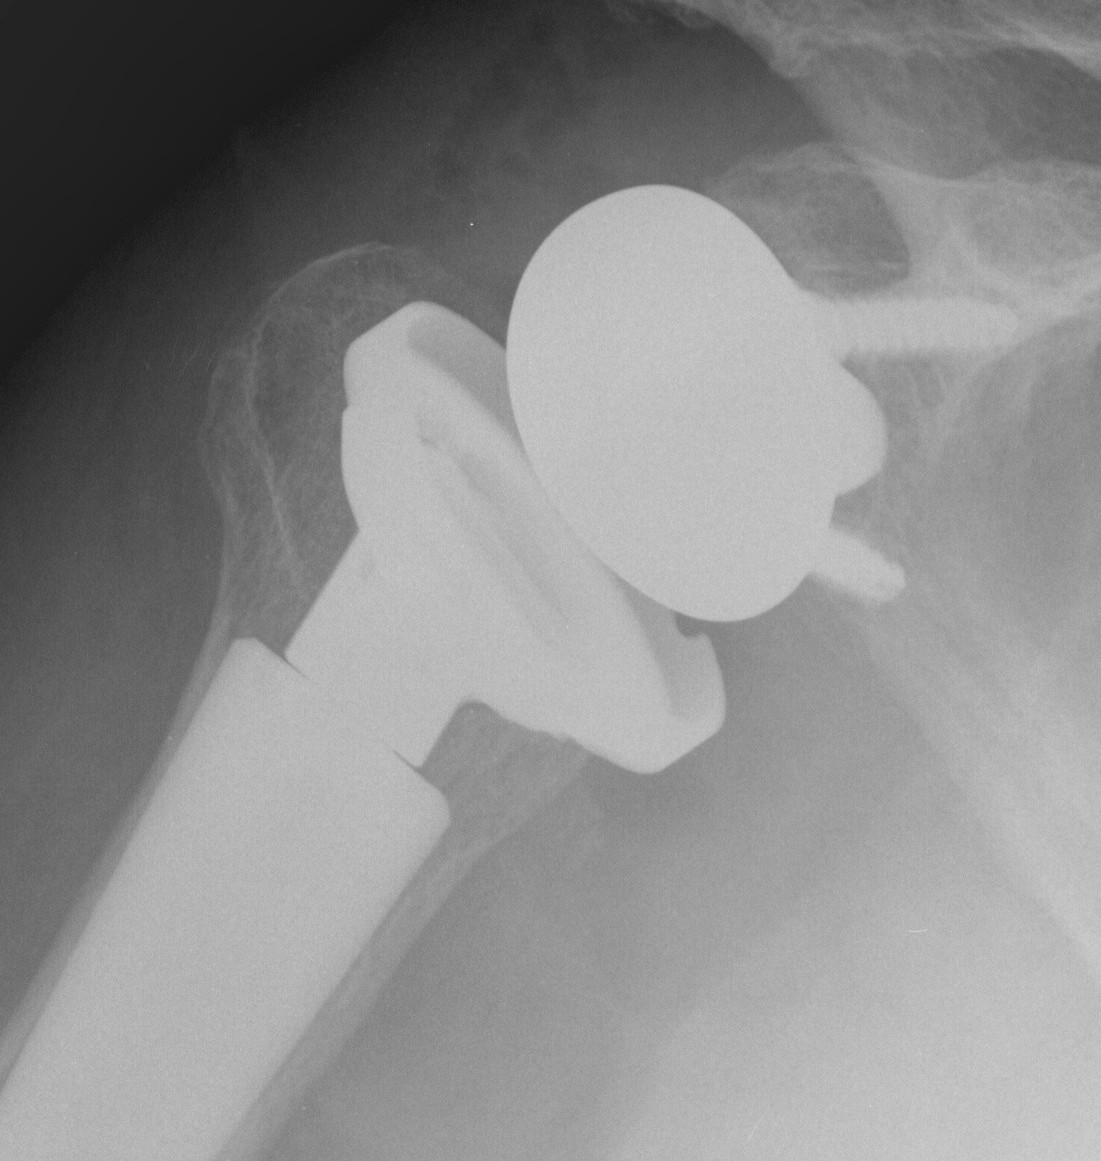

Reverse shoulder arthroplasty

Reverse

- socket in proximal humerus

- ball in glenoid

- center of rotation shifted medially and distally

- allows deltoid to apply compressive force and stabilize joint in absence of rotator cuff

Paul Grammont in 1985

- humeral component concave

- glenoid component / glenospere convex

- glenoid component uncemented with peripheral screws and central plug

- center of rotation shifted medially to glenosphere with humerus distal